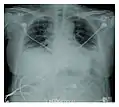

Rapid progression from initial symptoms to respiratory failure is a key feature. An x-ray that shows ARDS is necessary for diagnosis (fluid in the small air sacs (alveoli) in both lungs). In addition, a biopsy of the lung that shows organizing diffuse alveolar damage is required for diagnosis. This type of alveolar damage can be attributed to nonconcentrated and nonlocalized alveoli damage, marked alveolar septal edema with inflammatory cell infiltration, fibroblast proliferation, occasional hyaline membranes, and thickening of the alveolar walls. The septa are lined with atypical, hyperplastic type II pneumocytes, thus leading to the collapse of airspaces. Other diagnostic tests are useful in excluding other similar conditions, but history, x-ray, and biopsy are essential. These other tests may include basic blood work, blood cultures, and bronchoalveolar lavage.

Acute interstitial pneumonia showing a marked reduction in lung capacity_Idiopathic_DAD_3.jpg.webp)